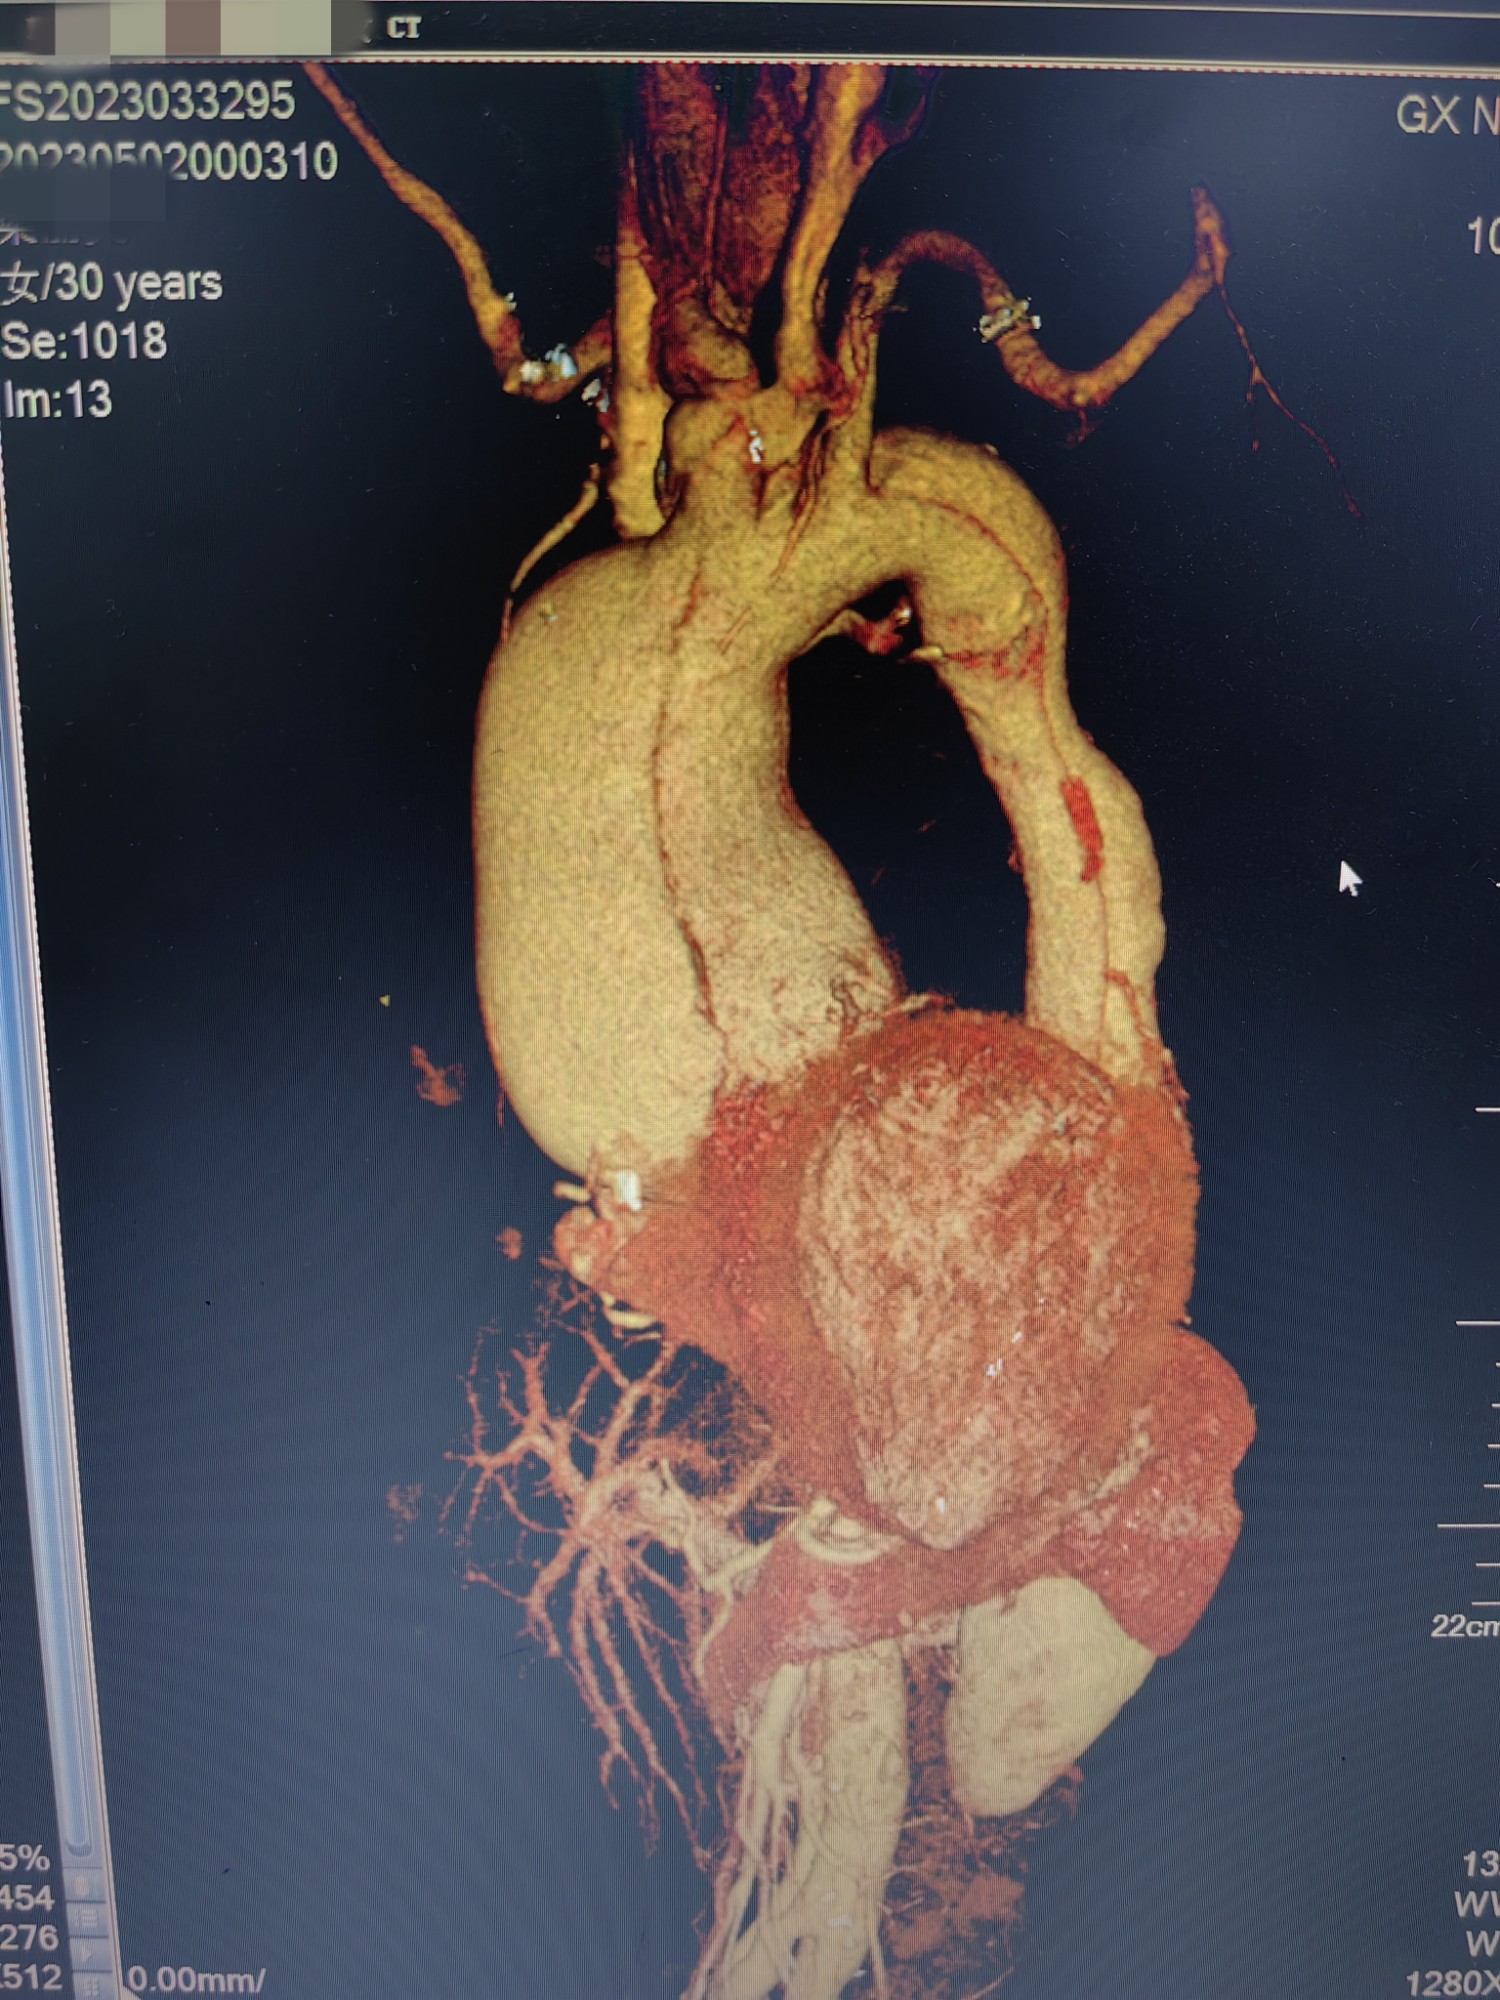

俗语说:“麻绳专挑细处断,噩运只找苦命人”。2023年4月底,李女士开始出现活动后气促、心悸症状,夜间阵发性呼吸困难,只能端坐呼吸,不能平卧睡眠。她自行口服感冒药后症状也迟迟没得到缓解,于是到广西壮族自治区南溪山医院心血管内科住院治疗,却不幸被确诊为A型主动脉夹层及马凡综合征,被紧急转到心脏大血管外科。CT血管造影(CTA)检查提示李女士为A型主动脉夹层(慢性),升主动脉增粗接近10cm,而健康人群的主动脉只有3cm左右;左冠状动脉上方有3cm的巨大主动脉破口,右冠状动脉则是直接内外膜离断,主动脉远端真腔受压极小。

2、手脚细长、血压脉压差很大、术前CTA三维、根部严重扩张。(1)

3、手脚细长、血压脉压差很大、术前CTA三维、根部严重扩张。 (2)

4、手脚细长、血压脉压差很大、术前CTA三维、根部严重扩张。 (3)

5、手脚细长、血压脉压差很大、术前CTA三维、根部严重扩张。(4)